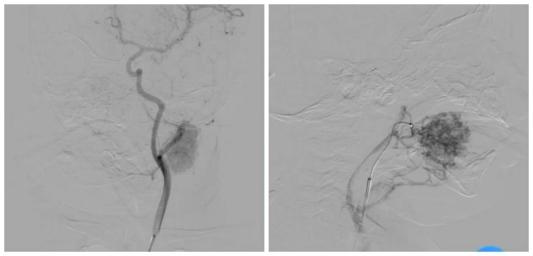

针对该患儿的病情特点与治疗需求,张庆彪主任携手刘海滨副主任医师,带领团队开展多学科术前评估、影像学分析及方案论证,最终确定采用DSA引导下介入硬化治疗方案。手术中,医疗团队依托DSA设备的实时动态成像与“精准导航”功能,经患儿股动脉穿刺建立微创通道,将微导管、导丝精准送达面部血管瘤供血动脉主干,在透视下缓慢注入硬化剂,使病灶血管内皮细胞坏死、管腔闭塞,实现“靶向根治”效果。整个手术过程历时短、创伤仅为穿刺点大小,术后患儿生命体征平稳,病灶即刻呈现萎缩趋势,疗效立竿见影。

DSA引导下血管瘤介入硬化治疗是血管介入领域的前沿技术,其核心优势在于精准定位、微创操作、恢复迅速、无明显瘢痕残留,尤其适配面部等对美观要求极高的部位病变。目前,该项技术在山东省内儿科领域尚属少数医院开展,临沂市人民医院此次首例手术的成功实施,不仅填补了区域内儿童面部血管瘤精准微创治疗的空白,为鲁南、苏北地区血管瘤患儿带来了更优质的医疗选择,更彰显了医院“技术创新驱动学科发展”的核心理念,进一步提升了医院在儿童介入医学领域的学科竞争力,强化了区域医疗中心的技术辐射与服务能力,未来将为更多患儿及家庭带来康复福音。(通讯员 胡志鲁 刘海滨)